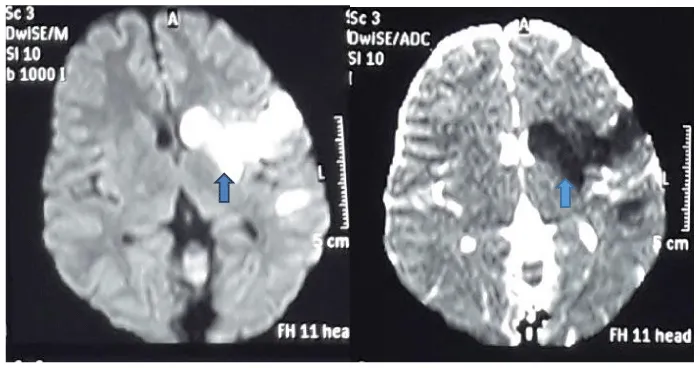

Computed Tomography (CT) scan was normal. Magnetic Resonance Imaging (MRI) of the brain showed left sided middle cerebral artery territory infarct (Figure 1).